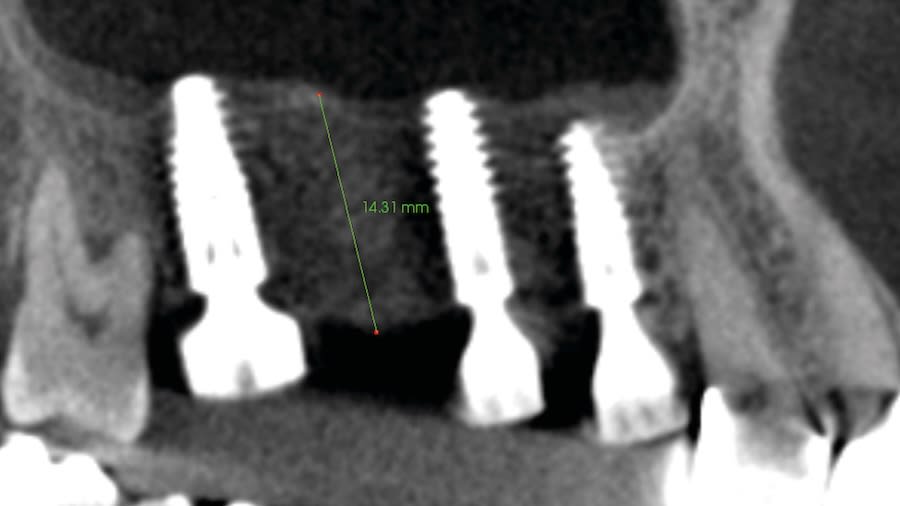

Step 4: Allow 4 to 6 months for the sinus graft healing. CBCT evaluation is needed to evaluate the available regenerated bone height for the implant placement. Reflect soft tissue utilizing standard surgical instruments, and use Densah burs for osseodensification site preparation to prepare the implant osteotomy and place the implant.

Case 1 (Figure 3 through Figure 24) depicts a 3-year follow-up of combined osseodensification sinus protocol IV in a severely resorbed maxillary ridge with ≤0.5 mm bone height in molar sites and horizontal deficiency at the first premolar site, using a two-stage approach for implant placement.

Case 2 (Figure 25 through Figure 36) illustrates a 3-year follow-up of the osseodensification sinus protocol IV in a severely resorbed right maxillary ridge with <0.5 mm bone height in molar sites, using a two-stage approach for implant placement.

Case 3 (Figure 37 through 44) shows a case of significant trauma history with a 3-year follow-up of the osseodensification sinus protocol IV in a severely resorbed right maxillary ridge with ≤0.5 mm bone height in molar sites, using a two-stage approach for implant placement.